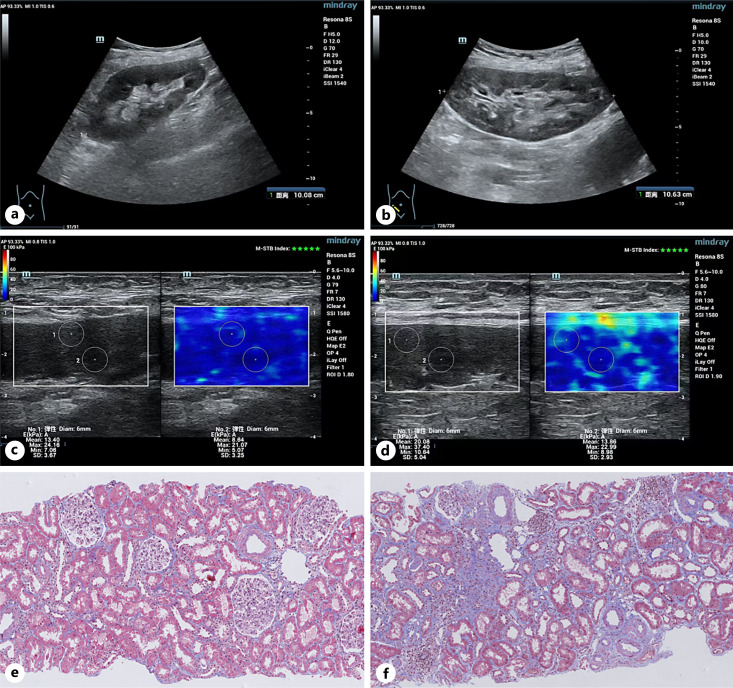

Introduction: Shear-wave elastography (SWE) is a promising noninvasive technique for measuring renal fibrosis after transplantation. This study aimed to develop an interpretable model to predict allograft deterioration in kidney transplant recipients and evaluate the predictive ability of SWE features.

Methods: In this prospective cohort study, we performed SWE examinations on kidney transplant recipients at Renji Hospital between October 2020 and August 2023. The primary outcome was a composite of a 40% decline in estimated glomerular filtration rate or end-stage kidney disease. A total of 396 patients with stable renal allograft function were included. Five machine learning methods were used to construct predictive models.

Results: Among all participants, 69 (17.4%) individuals reached the outcome. The XGBoost model with the addition of SWE features achieved the highest predictive performance with 20 repeats of nested tenfold cross-validation AUC of 0.870 (95% CI: 0.862-0.878) in the training dataset and 0.868 (95% CI: 0.801-0.935) in the validation dataset. Patients with higher medullary or cortical tissue stiffness had worse prognoses. A high level (>10 kPa) of medullary SWE was an independent risk predictor (adjusted OR, 2.68; 95% CI, 1.12-6.41).

Conclusion: The joint use of SWE parameters and laboratory data significantly improved the risk prediction performance for a faster decline in allograft function. This interpretable XGBoost model may provide a readily available system to guide patient monitoring using noninvasive methods.